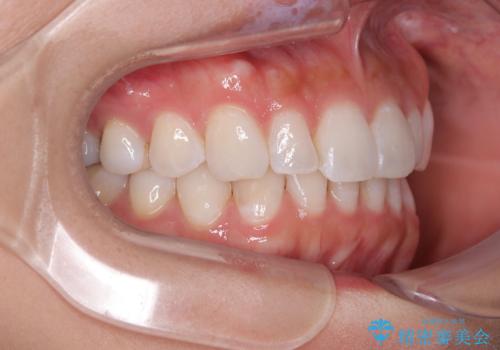

【モニター】前歯のデコボコと小さい前歯 インビザライン矯正とオールセラミッククラウン補綴治療

- 前歯の歯並びと生えてきたときから小さい前歯を気にして来院された患者様です。

上下前歯の歯列不正はインビザラインにより整え、その後に、矮小歯の前歯をオーダーメイドタイプのオールセラミッククラウンにて補綴治療することとしました。

インビザライン矯正の場合、矮小歯を矯正治療後にセラミックとするかどうかを矯正治療開始前に決める必要があるため、悩んでしまう方が多いです。

セラミッククラウンにて大きさを変更することを前提に矯正治療を開始したため、大変満足のいく仕上がりとなりました。